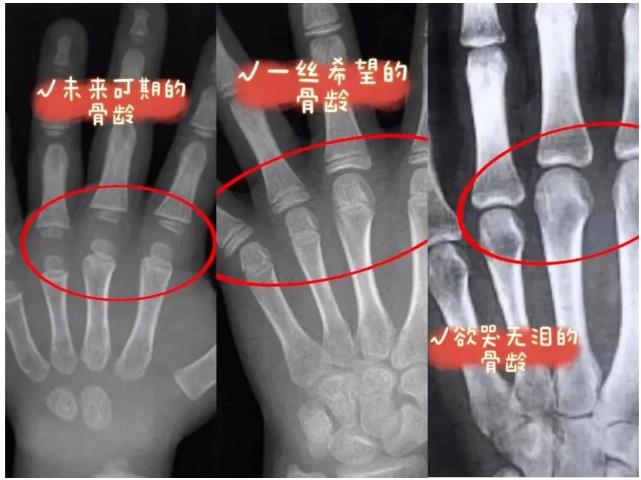

骨龄,评价孩子身高的“金标准”

身高由长骨决定,人类骨骼生长发育的变化过程基本相似,每一根骨头的发育过程都具有连续性和阶段性。不同阶段的骨头具有不同的形态特点。

所以,骨龄不仅可以确定儿童的生物学年龄,还可以及早了解儿童的生长发育潜力以及性成熟的趋势,并能比较科学地预测儿童的成年身高。因此,想要准确了解孩子长得好不好,知道将来能长多高都离不开骨龄。

什么是骨龄?

骨龄就是骨骼的年龄,一般会和生理年龄(即“周岁”)有一定偏差。